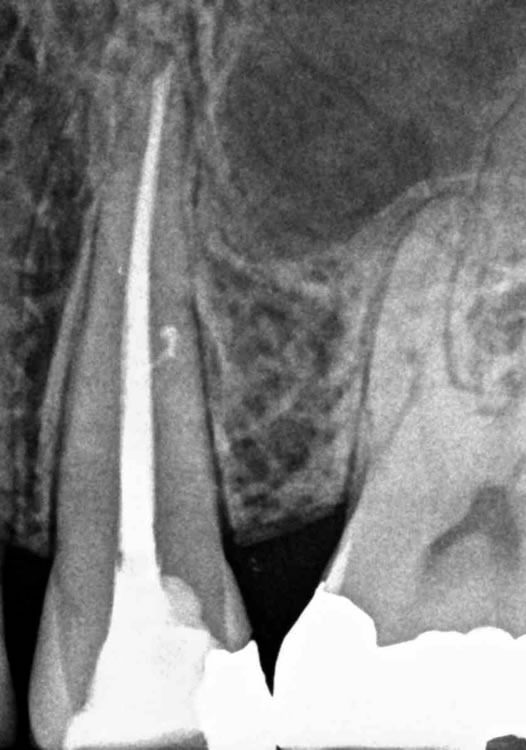

Terapia endodontica di un dente in pulpite

Premolare superiore di sinistra in pulpite (infiammazione acuta della polpa).

Si è resa necessaria la terapia endodontica.

L'elemento verrà poi ricostruito e successivamente protesizzato.